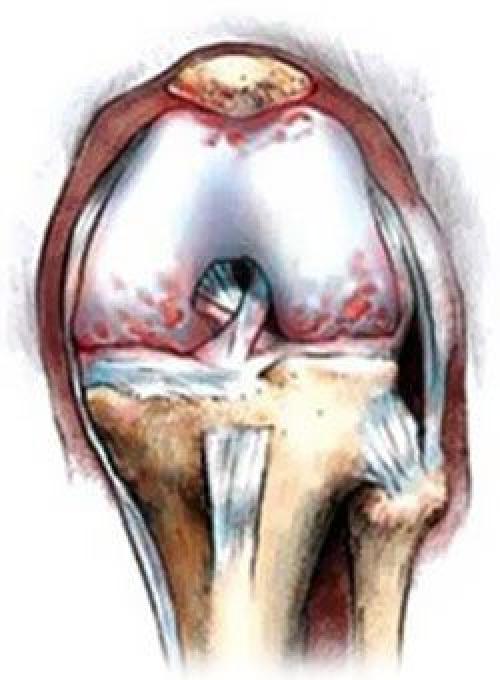

При артрозе истончается хрящевая соединительная ткань сустава, тем самым травмируя кости

При лечении артроза колена следует подобрать правильный комплекс мер для излечения болезни. В первую очередь следует установить правильный диагноз. Чем раньше будет начато лечение, тем больше шансов на быстрое выздоровление. Обезболивающие средства следует принимать только по назначению врача. При нарушении хрящевой ткани коленного сустава принимают хондопротекторы, благодаря которым идет быстрое восстановление поврежденных хрящевых тканей. Дополнительно принимают согревающие мази, противовоспалительные кремы и сосудорасширяющие препараты. Лечащий врач может назначить накладывание различных компрессов на болезненный сустав, а также инъекции и физиопроцедуры.

Не стоит забывать, что медикаментозные средства не лечат артроз коленного сустава, а лишь помогают избавиться от неприятных симптомов заболевания. Многие из них имеют побочные действия, и длительное их использование нежелательно.